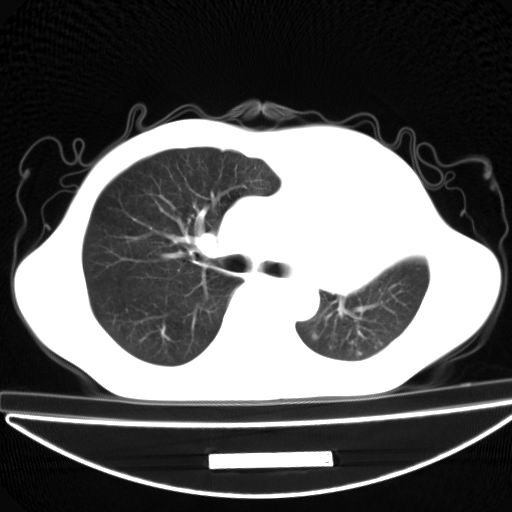

以下是引用杀毒软件在2009-4-28 17:58:00的发言:[br]考虑----左肺慢性肺脓肿形成继发上叶含气不良---抗炎后复查---待排肿瘤所致[br][br][本贴已被 杀毒软件 于 2009-4-28 18:01:26 修改过]